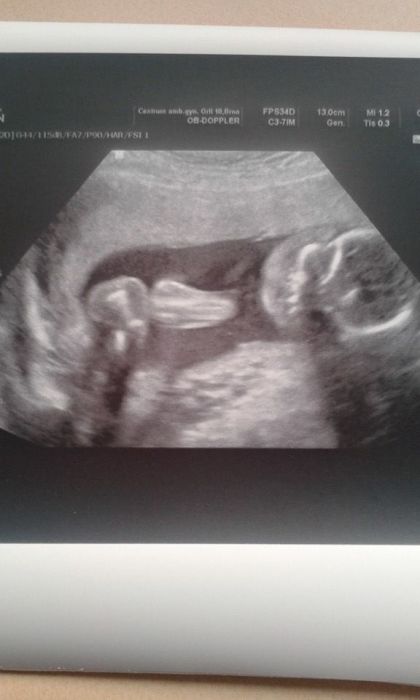

a takto dnešní poradna dopadla. Broucek necekane spinkal (vždck na utz jen spí,max se protáhne nebo přetočí),takze jsme na utz kozkaly s pani Dr jak ziva

Jinak vse v poradne,srdicko krasne tluce a potvrzen chlapecek (jen na utz to bylo lepe videt nez na fotecce).Navic neni asi fotogenicky,takze ani jedna fotecka neni nic extra.Placentu mam vepredu,proto citim tak malo a slabe prdolku. Cítím ho totiž spíš jako žížalku a hlavně dole v podbřišku a nejlépe když mám skrčené nohy. Zrovna ted se tam ozývá jak pííši.S vahou jsme se dostali na vychozi vahu,takze k dnesku +0kg (jinak je to +1,5-2kg). Velky utz nechan tedy na 17.3. a dalsi poradna 3.4. takze ted uvidim Filipka kazdych 14 dni